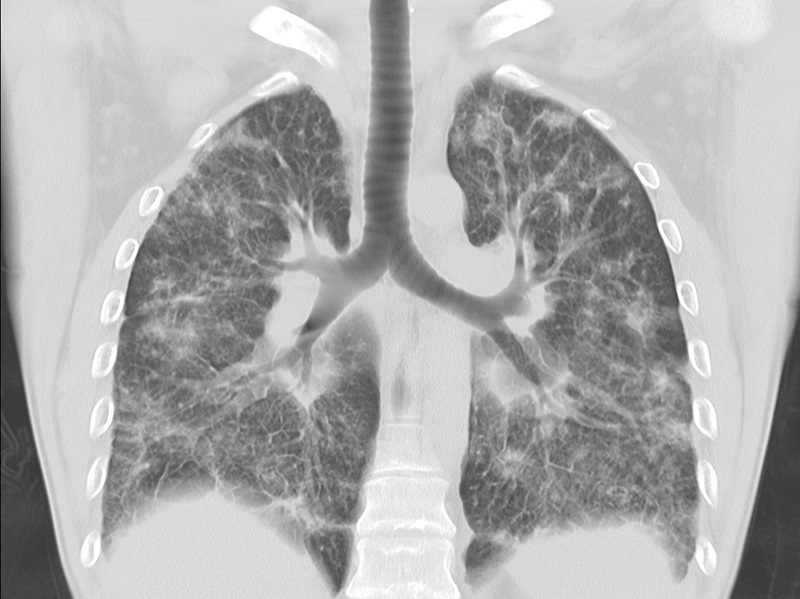

Одно из главных условий сохранения здоровья легких, а соответственно и жизни, — ежегодный флюорографический осмотр. Туберкулез по-прежнему находится в первой десятке болезней, уносящих миллионы жизней по всему миру.